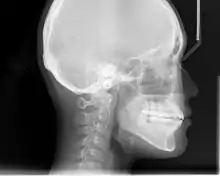

An X-ray taken for skull analysis

In the postwar period, cephalometric radiography[12] started to be used by orthodontists for measuring changes in tooth and jaw position caused by growth and treatment.[13] The x-rays showed that many Class II and III malocclusions were due to improper jaw relations as opposed to misaligned teeth. It became evident that orthodontic therapy could adjust mandibular development, leading to the formation of functional jaw orthopedics in Europe and extraoral force measures in the US. These days, both functional appliances and extraoral devices are applied around the globe with the aim of amending growth patterns and forms. Consequently, pursuing true, or at least improved, jaw relationships had become the main objective of treatment by the mid-20th century.[6]